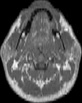

Visible Human male: Sectio transversalis 1194

CT

NMR

Pd T1 T2